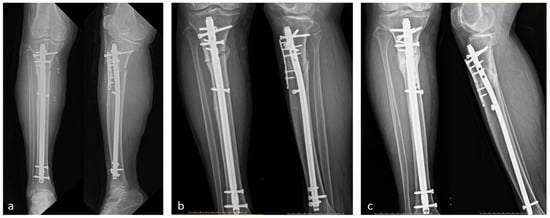

2. Case Presentation